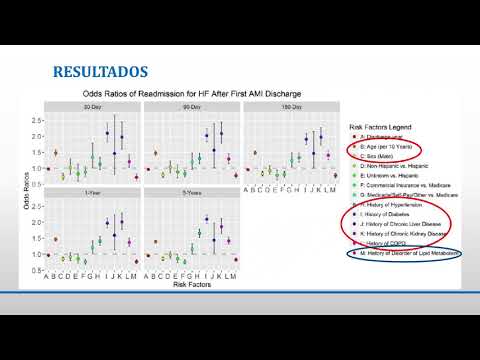

Factores de riesgo asociados con eventos cardiovasculares mayores durante el primer año post IAM. Dra. Sofía Gabriela Rodríguez. Residencia de Cardiología. Hospital C. Argerich. Buenos Aires